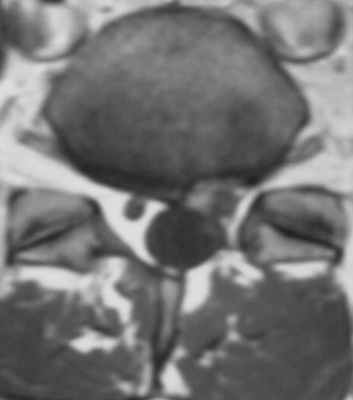

(Слева) Аксиальный срез, Т1-ВИ: правосторонний гемиляминэктомический дефект и утолщение правой дуральной воронки корешка с ее периферическим контрастным усилением, связанное с цикатризацией.

(Справа) На аксиальном Т1-ВИ определяется небольшой левосторонний гемиляминэктомический дефект. Левый корешок S1 окружен мягкотканными изменениями, которые тем не менее не оказывают объемного воздействия на дуральный мешок.